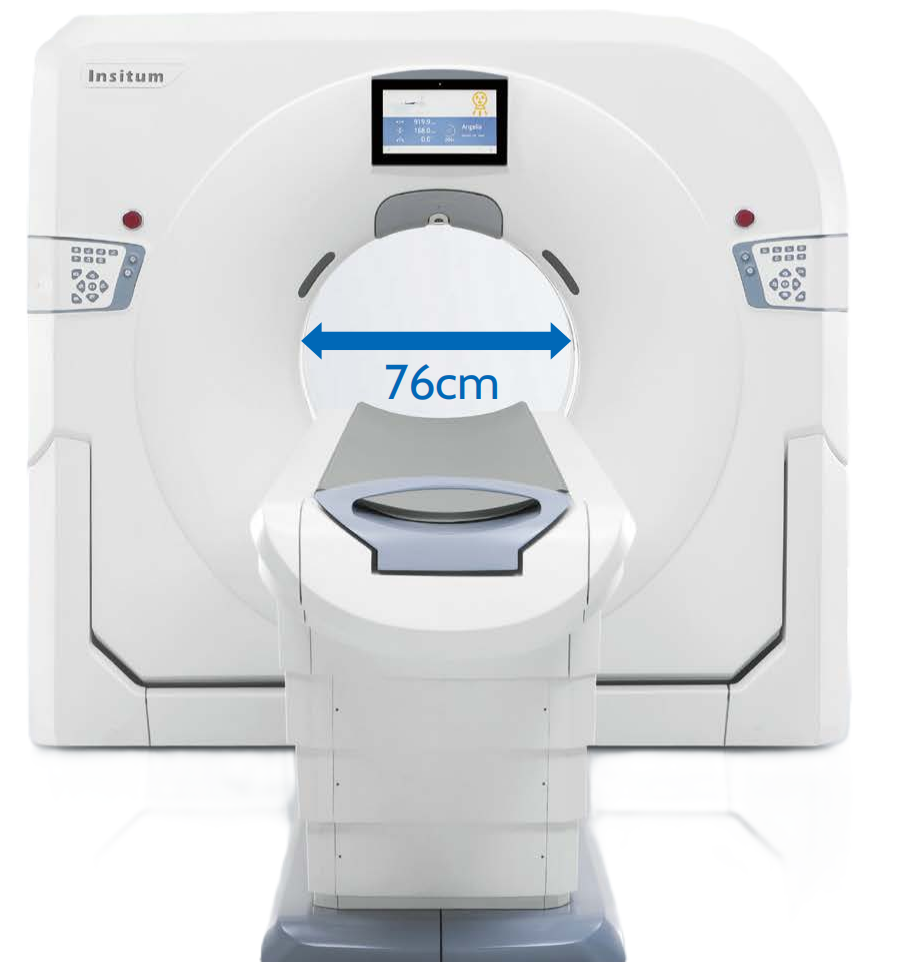

SinoVision Insitum 16/32 - это 32 срезовый КТ с большой апертурой гентри 75см. Подходит под рутинные и детальные диагностические исследования под контролем КТ, используемые для малоинвазивных вмешательств

SinoVision Insitum 16 - это 16 срезовый КТ с апертурой гентри 76см.

- Апература 76 см и увеличенное пространство сканирования позволяют расширить сферу применения оборудования.

Клиническая эффективность Insitum 16-высокоскоростное сканирование и широкая апертура гентри.

Широкая апертура гентри позволяет снизить уровень тревожности и упростить обследование пациентов, страдающих клаустрофобией. Для клинического использования большое пространство в гентри дает возможность сканировать пациента с применением дополнительных устройств, а также проводить малоинвазивные вмешательства под контролем КТ.

- Диаметр апертуры гентри: 76 см

- Диаметр апертуры гентри: 76 см